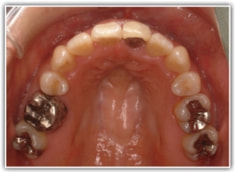

治療後(2年3ヶ月後)

歯根のパラレリング(平行性)が獲得されております。

下顎8番は、両側抜歯済みです。